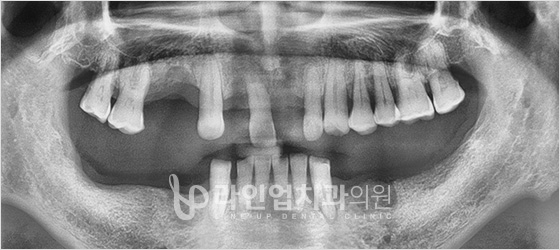

치료전

Before

치료후

After

아래 어금니 임플란트 (59세/남/ 2015.07.08~2016.02.04)